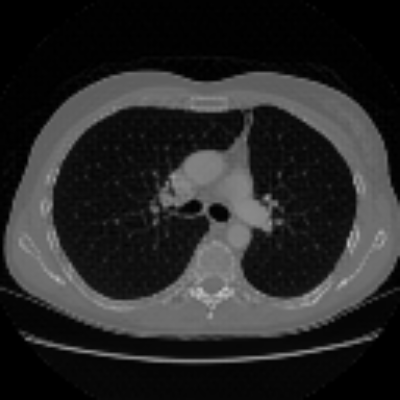

| Axial | Coronal | Sagittal | |

| X2CTGAN | ![]() |

![]() |

|

| DX2CT | ![]() |

| Ground-truth | ![]() |

Figure 3 and Table I(a) using biplanar X-rays show that proposed DX2CT can outperform three existing SOTA methods. Figure 3 shows that DX2CT can provide more accurate overall shapes and details compared to the existing methods. The quality of reconstructed CT slices in the axial plane is less satisfactory than those in the other planes. The reason is that the axial plane is perpendicular to the planes of biplanar X-rays so there exists less spatial (i.e., depth) information in the axial plane. Without using the perceptual loss [33], proposed DX2CT gave comparable LPIPS results with PerX2CTs using [33] in training. Compare their LPIPS results in Table I(a).